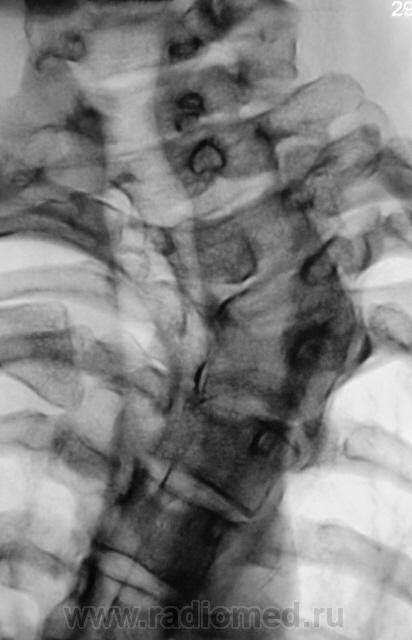

Это синостоз тел верхних шейных позвонков и С6-С7? И боковые клиновидные полупозвонки в верхнегрудном отделе? Это синдром Клиппеля-Файля? А может и Шпренгеля...

Поражает, что только сейчас выявлена такая выраженная дисплазия..там видимо и по органам проблемм хватает..

Совершенно верно. Ведь детей и подростков "смотрят" каждый год. Возникает вопрос, как смотрят и каким "органом"?